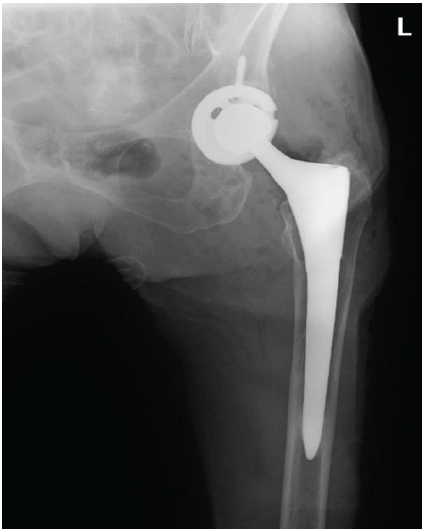

Given the failed reductions and the development of neurological deficits, the decision was made to proceed with an open reduction. During the procedure, it was found that the femoral head had penetrated through the gluteus medius muscle, impeding reduction (Fig. 2). In addition, the sciatic nerve was abutting the posterior acetabulum and was entrapped in scar tissue (Fig. 3).

Figure 2: Clinical photograph during open reduction with the head violating the abductors.

Neurolysis was performed to release the sciatic nerve, and the femoral head was carefully disengaged from the muscle. The acetabular and femoral prosthetic components were assessed and deemed to be stable and thus were left in position. The femoral head size was increased from +4 to +8 (32 mm head) to enhance stability (Figs. 4 and 5).

Figure 4: Post-reduction X-ray of left hip.